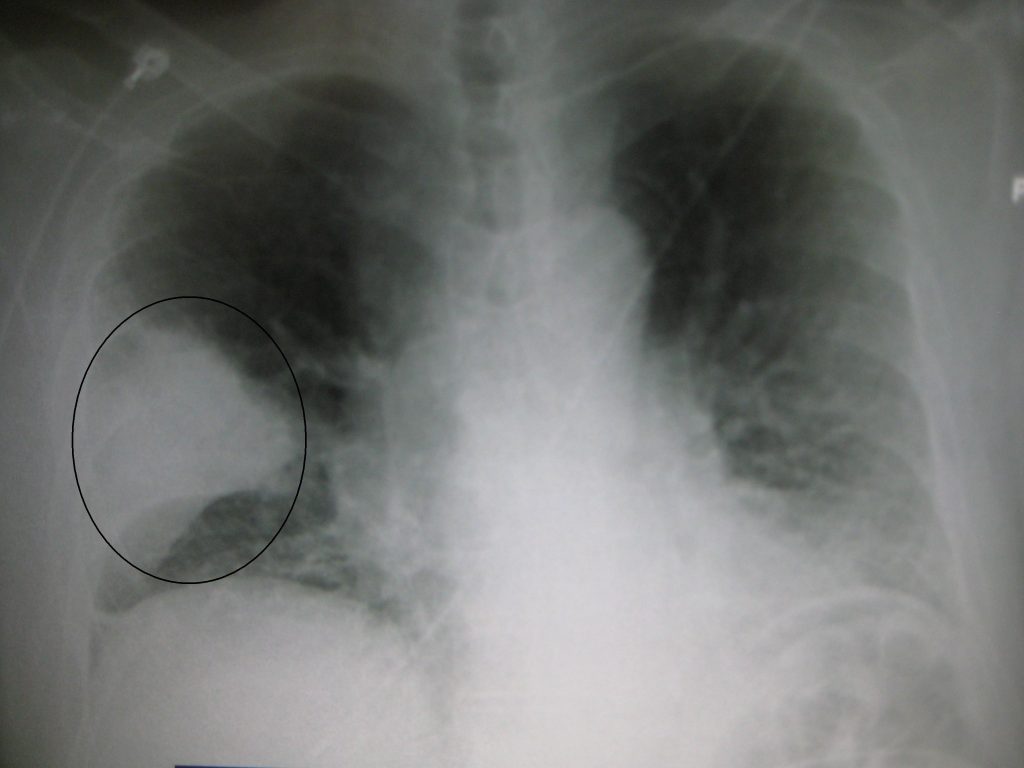

En vísperas del Día Mundial contra la Neumonía, que se conmemora cada 12 de noviembre, el especialista dijo a periodistas que esta infección pulmonar bacteriana se puede contraer en cualquier lugar y etapa de la vida, pero resulta más letal en adultos mayores, niños menores de cinco años y personas con factores de riesgo.

De acuerdo con la Organización Mundial de la Salud (OMS), la neumonía puede estar causada por virus, bacterias u hongos.